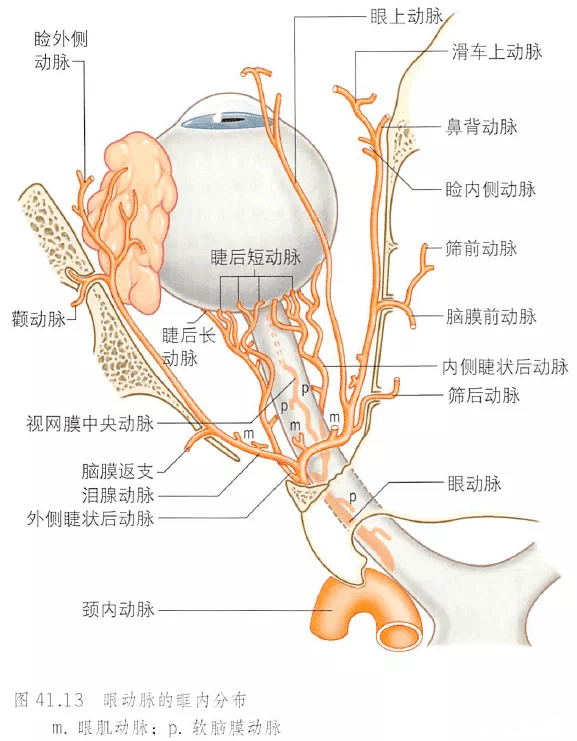

发病机制眼动脉的分支有睫状前动脉,睫状后动脉,泪腺动脉,滑车上动脉

视神经的外侧,然后在上直肌的下方越至眼眶的内侧前行,终于滑车上动脉

图l面部血管示意4.防治策略目前对于失明病例尚无成熟的治疗方法.